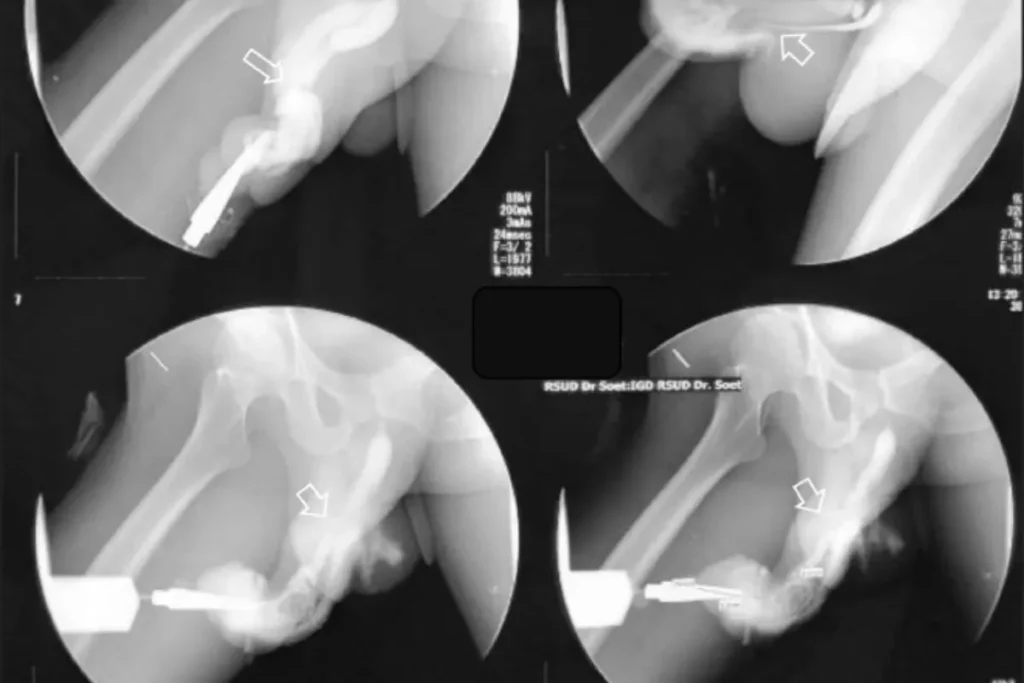

「陰莖骨折」雖然聽起來嚇人,但其實並不是陰莖裡有骨頭。它是指陰莖在勃起狀態下受到劇烈彎曲撞擊,導致陰莖海綿體的白膜(tunica albuginea)破裂,是一種需要立即就醫的泌尿急症。

大多數陰莖骨折需要透過手術修補破裂的白膜組織,並視情況修補尿道。如果治療及時,恢復情況良好,性功能多數能恢復正常。

※黃金治療時間:24 小時內手術效果最佳,延誤可能導致永久性勃起障礙或陰莖變形。